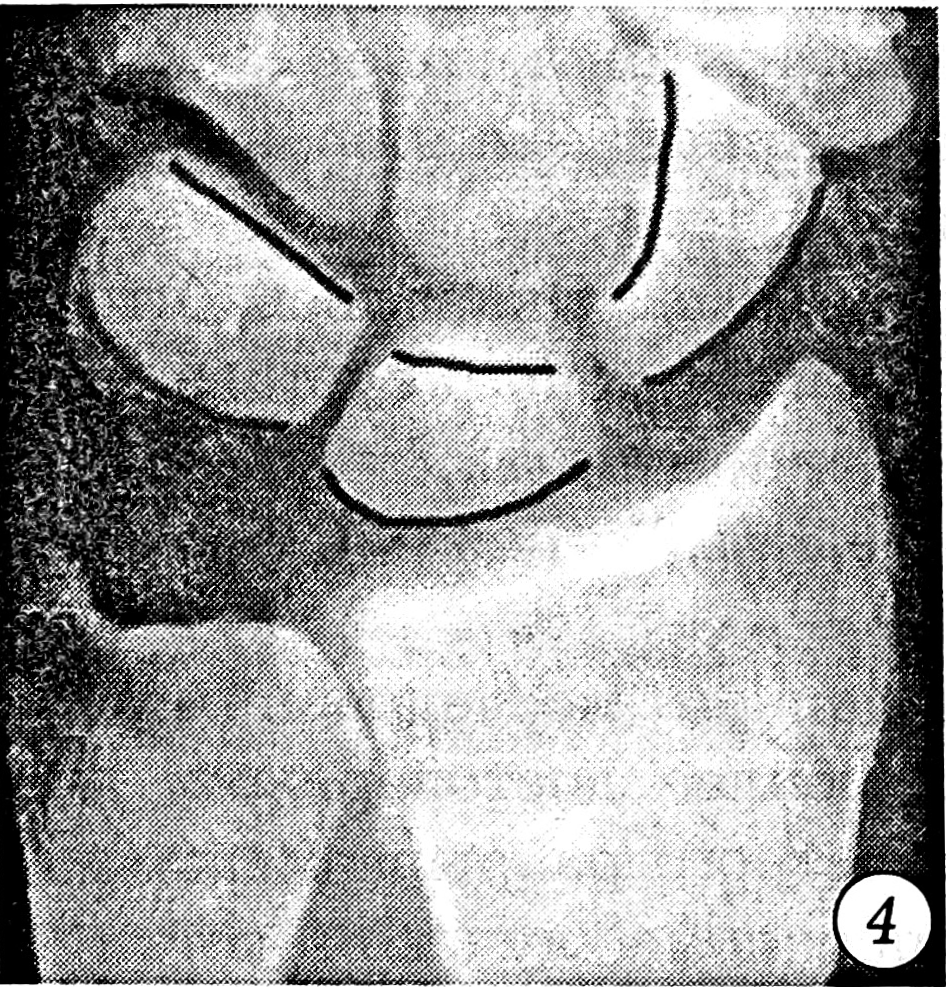

Исследовались первичные рентгенограммы и контрольные, сделанные после выполнения репозиции. Отбирались те случаи, в которых хотя бы на одном снимке присутствовали один или несколько из следующих рентгенологических признаков повреждения межзапястных связок: увеличение полулунно-ладьевидного угла более чем до 70° (рис. 1), симптом «кольца» дистального полюса ладьевидной кости (рис. 2), изменение формы и расширение полулунно-ладьевидного промежутка до 3 мм и более (рис. 3), нарушение непрерывности трех «запястных арок» (рис. 4), расширение полулунно-трехгранного промежутка (рис. 5) и увеличение полулунно-головчатого угла более чем до 20° (рис. 6) [5]. Результаты исследования представлены в табл. 1.

Рис. 4. Нарушение непрерывности «запястных арок».